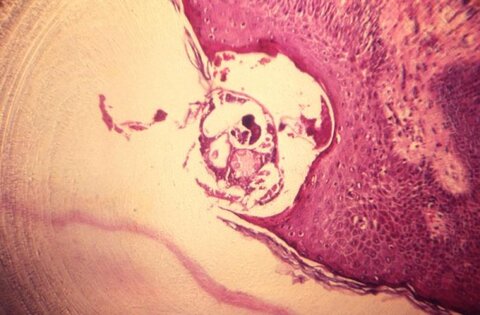

The research, co-authored by the London School of Hygiene & Tropical Medicine (LSHTM), Brighton and Sussex Medical School (BSMS) and Public Health England, studied scabies outbreaks in 10 elderly care homes in the South East of England. The team found that among older people, scabies symptoms were often found on parts of the body normally covered by clothes, rather than on the hands, where healthcare professionals tend to look for them. Additionally, residents with dementia were often unable to report symptoms of itching, meaning their condition was missed.

During the 10 outbreaks studied, which occurred over a period of 15 months, dermatology-trained physicians examined 230 residents with a median age of 86.9 years, 157 of whom had dementia. Over a quarter of residents examined (26.5%) were diagnosed with scabies, and more than half of those diagnosed (57.4%) only had signs on areas of the body that would normally be covered. The odds of receiving a scabies diagnosis were increased 2.4 times for residents with dementia.